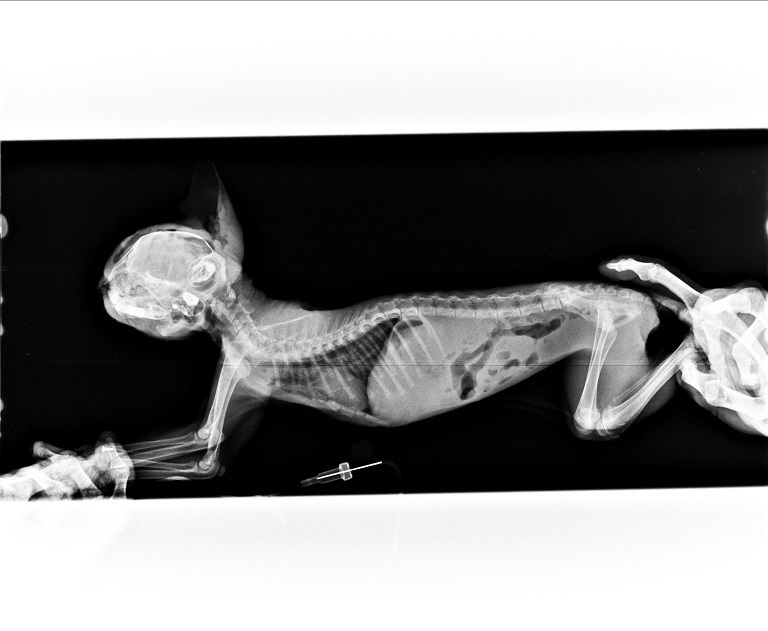

主題: 被門夾到頭導致嚴重外傷的Bebo 申請者姓名: 臺北市支持流浪貓絕育計劃協會 花色: 申請日期: 2016-10-29 22:39:51 申請者部落格: 申請者臉書網址: 所在縣市/合作醫院: 台北市/其他院所醫助專案(醫院請先MAIL溝通) 治療費用: 82764元 需求人數: 85人 已結案 (2022-05-13 15:21:28) 報名人員: Pond Kao(已付款)、Yi-Ling Yao(已付款)、chucl(已付款)、菲小比(已付款)、鄭余丞(已付款)、Mandy Chen(已付款)、陳哈君(已付款)、Eva Huang(已付款)、Monica Wang(已付款)、林冠霖(已付款)、Fiona Cheng(已付款)、Viana Lin(已付款)、回向給貓咪拿鐵 x2(已付款)、Hikaru x2(已付款)、阿菜(已付款)、Becca(已付款)、maggie(已付款)、jc0918 x2(已付款)、無名氏(已付款)、Heidi Shih x5(已付款)、Julling Hu(已付款)、若、Estee x2(已付款)、Shih-Wei(已付款)、Joanna Hu(已付款)、布蕾(已付款)、Morca Tsai、Moni(已付款)、寶妮(已付款)、米薇安(已付款)、Wenny Chen x2(已付款)、羅曉筑(已付款)、FiFi(已付款)、Sunny Yang(已付款)、masae(已付款)、Emma Lai(已付款)、Iris(已付款)、Vita(已付款)、connie(已付款)、Forest(已付款)、Jenny Lo(已付款)、toolong(已付款)、Jacka(已付款)、Erin Lin(已付款)、DannyChen x2(已付款)、薇薇安(已付款)、Irene Lee(已付款)、摘星星(已付款)、仲希妍(已付款)、Joe Ho(已付款)、徐子晴(已付款)、Dai Chen(已付款)、吳麗花(已付款)、Mia Chao(已付款)、Fei(已付款)、Becca Huang(已付款)、Ting Huang(已付款)、Sally Lin(已付款)、Ciara Ting(已付款)、Lori Chao(已付款)、Stephy An(已付款)、Van(已付款)、coolan(已付款)、Joe Hook(已付款)、pia、purple(已付款)、Mileena x2(已付款)、Sheng Lin(已付款)、Po-Lin Chen x2(已付款)、維尼(已付款)、Sunny Lin(已付款)、angela(已付款)、Ning(已付款)、Ray0322(已付款)、RAI MA x2(已付款)、 候補人員: 動物病情說明: Bebo是被鐵門重重夾到頭的重傷小貓,

在緊急送到醫院時,

幾乎面目全非的Bebo卻還可以大口的吃飯,

強大的生存意志讓人感到不可思議!

Bebo的右耳幾乎全毀爛掉,

因此醫生將右外耳及耳道完全摘除。

頭臉上的皮膚有些破損壞死、有些則正常沒事,

醫生則將壞死的皮膚清創,

將正常的皮膚擴張整型覆蓋其他傷口,

在拉張整個臉皮後醫生預期Bebo的眼睛可能會變得難以張閉....

因Bebo的頭臉部手術相當複雜,

包括清創及擴張整形前後持續進行近一個月。